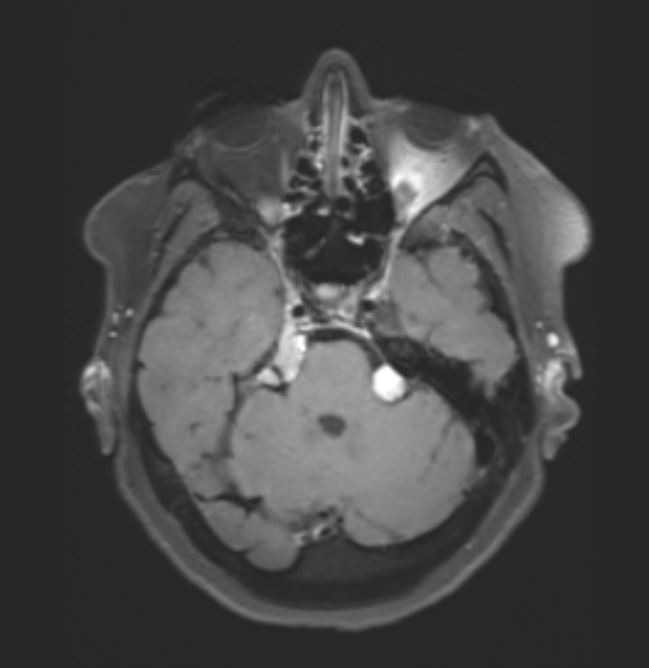

Η μαγνητική έδειξε ένα σχετικά μικρό ακουστικό νευρίνωμα αριστερά όμως η αιτία των προβλημάτων της ασθενούς ήταν ένα μηνιγγίωμα στην περιοχή της κορυφής του λιθοειδούς δεξιά το οποίο πίεζε το τρίδυμο νεύρο τόσο πριν όσο και εντός του Meckel’s cave (περιοχή του γαγγλίου του τριδύμου).

Αποφασίστηκε αρχικά η ακτινοχειρουργική αντιμετώπιση του ακουστικού νευρινώματος με ακτινοχειρουργική (SRS). Λίγες εβδομάδες μετά η ασθενής υπεβλήθη σε τροποποιημένη οπισθομαστοειδική κρανιοτομία (RISA – Retrosigmoid Intradural Suprameatal Approach) όπου η βλάβη αφαιρέθηκε ολικώς.

Η μετεγχειρητική μαγνητική τομογραφία ανέδειξε πλήρη εξαίρεση του όγκου (βλ εικόνες).

Η ασθενής είχε στην ουσία δύο όγκους: ένα ακουστικό νευρίνωμα (αιθουσαίο σβάννωμα) αριστερά και ένα μηνιγγίωμα σε μια ιδιαίτερα δύσκολα προσβάσιμη περιοχή του εγκεφάλου που λέγεται κορυφή του λιθοειδούς οστού (petrous apex) δεξιά.

Το μεγαλύτερο τμήμα του όγκου προσπελάσθηκε μέσω μιας τυπικής οπισθοσιγμοειδικής κρανιοτομίας όμως πρόβλημα αποτελούσε το τμήμα του όγκου το οποίο επεκτείνονταν στην περιοχή του γαγγλίου. Προκειμένω να αφαιρεθεί και αυτό το κομμάτι του όγκου “ανοίξαμε” την κορυφή του λιθοειδούς αφαιρώντας το οστικό έπαρμα ύπερθεν του εσω ακουστικού πόρου, μια απαιτητική και ιδιαιτερη τεχνική. Έτσι καταφέραμε την ολική εξαίρεση της βλάβης και την απαλλαγή της ασθενούς από τα συμπτώματά της.